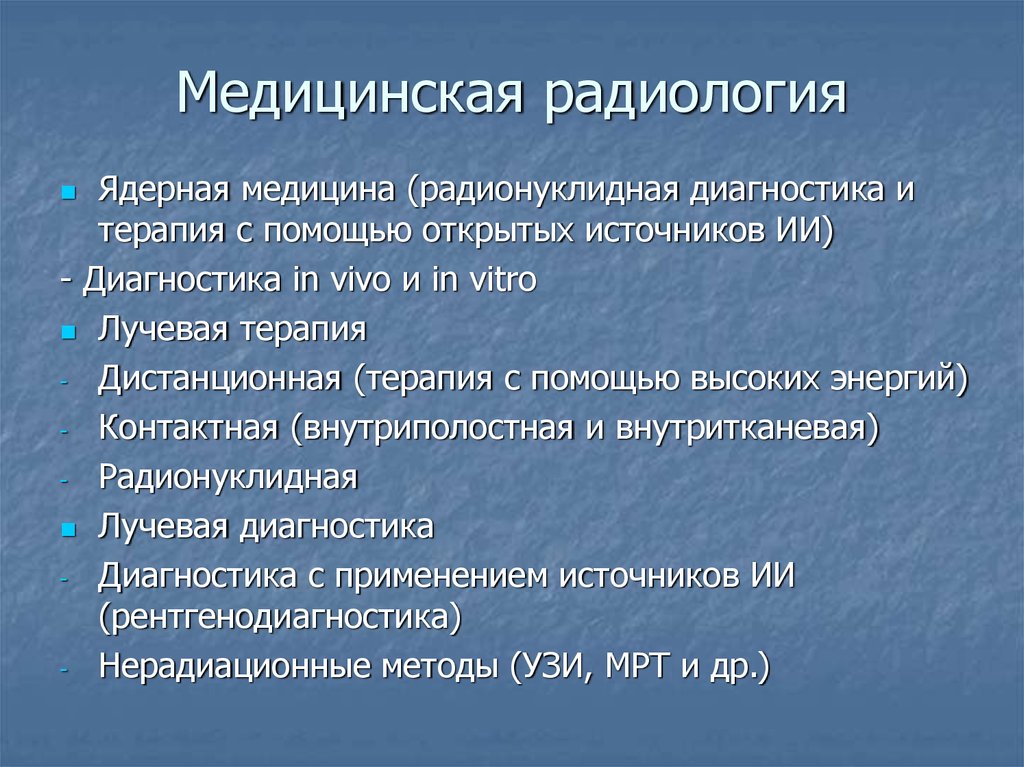

Радиология и радиотерапия? В чём разница. Ядерная медицина и лучевая терапия.